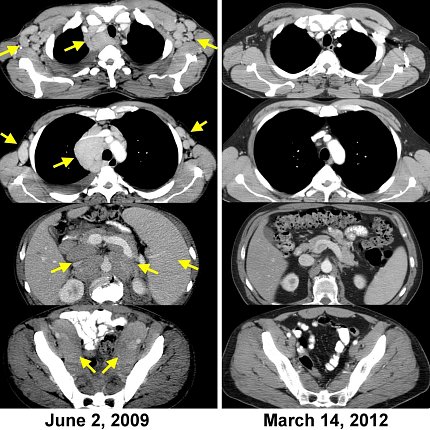

CAT-Scans des ersten Patienten, der auf die Behandlung durch adoptiven Transfer autologer Lymphozyten ansprach, die gentechnisch verändert wurden, um einen chimären Antigenrezeptor (CAR) zu exprimieren, der auf CD19 abzielt. Die linke Seite zeigt die Lymphombelastung; rechts: vollständige Krebsregression, die mehr als 10 Jahre später anhält.

Aufbauend auf langjährigen Studien und klinischen Studien ging Rosenbergs Forschung in zwei Richtungen. Man nutzt weiterhin patienteneigene natürliche Lymphozyten, die Krebs als lebendes Medikament erkennen können. Die zweite besteht darin, Immunzellen genetisch so zu verändern, dass sie Krebs bekämpfen. Tatsächlich war Rosenberg der erste Mensch, der einem Menschen fremde Gene einfügte und damit den Weg für das Gebiet der Gentherapie ebnete.

„Wir haben 2009 den ersten Patienten überhaupt behandelt, der diese CAR-T-Zellen erhielt. Er erlitt eine vollständige Rückbildung und ist mehr als 12 Jahre später krankheitsfrei“, sagte Rosenberg.